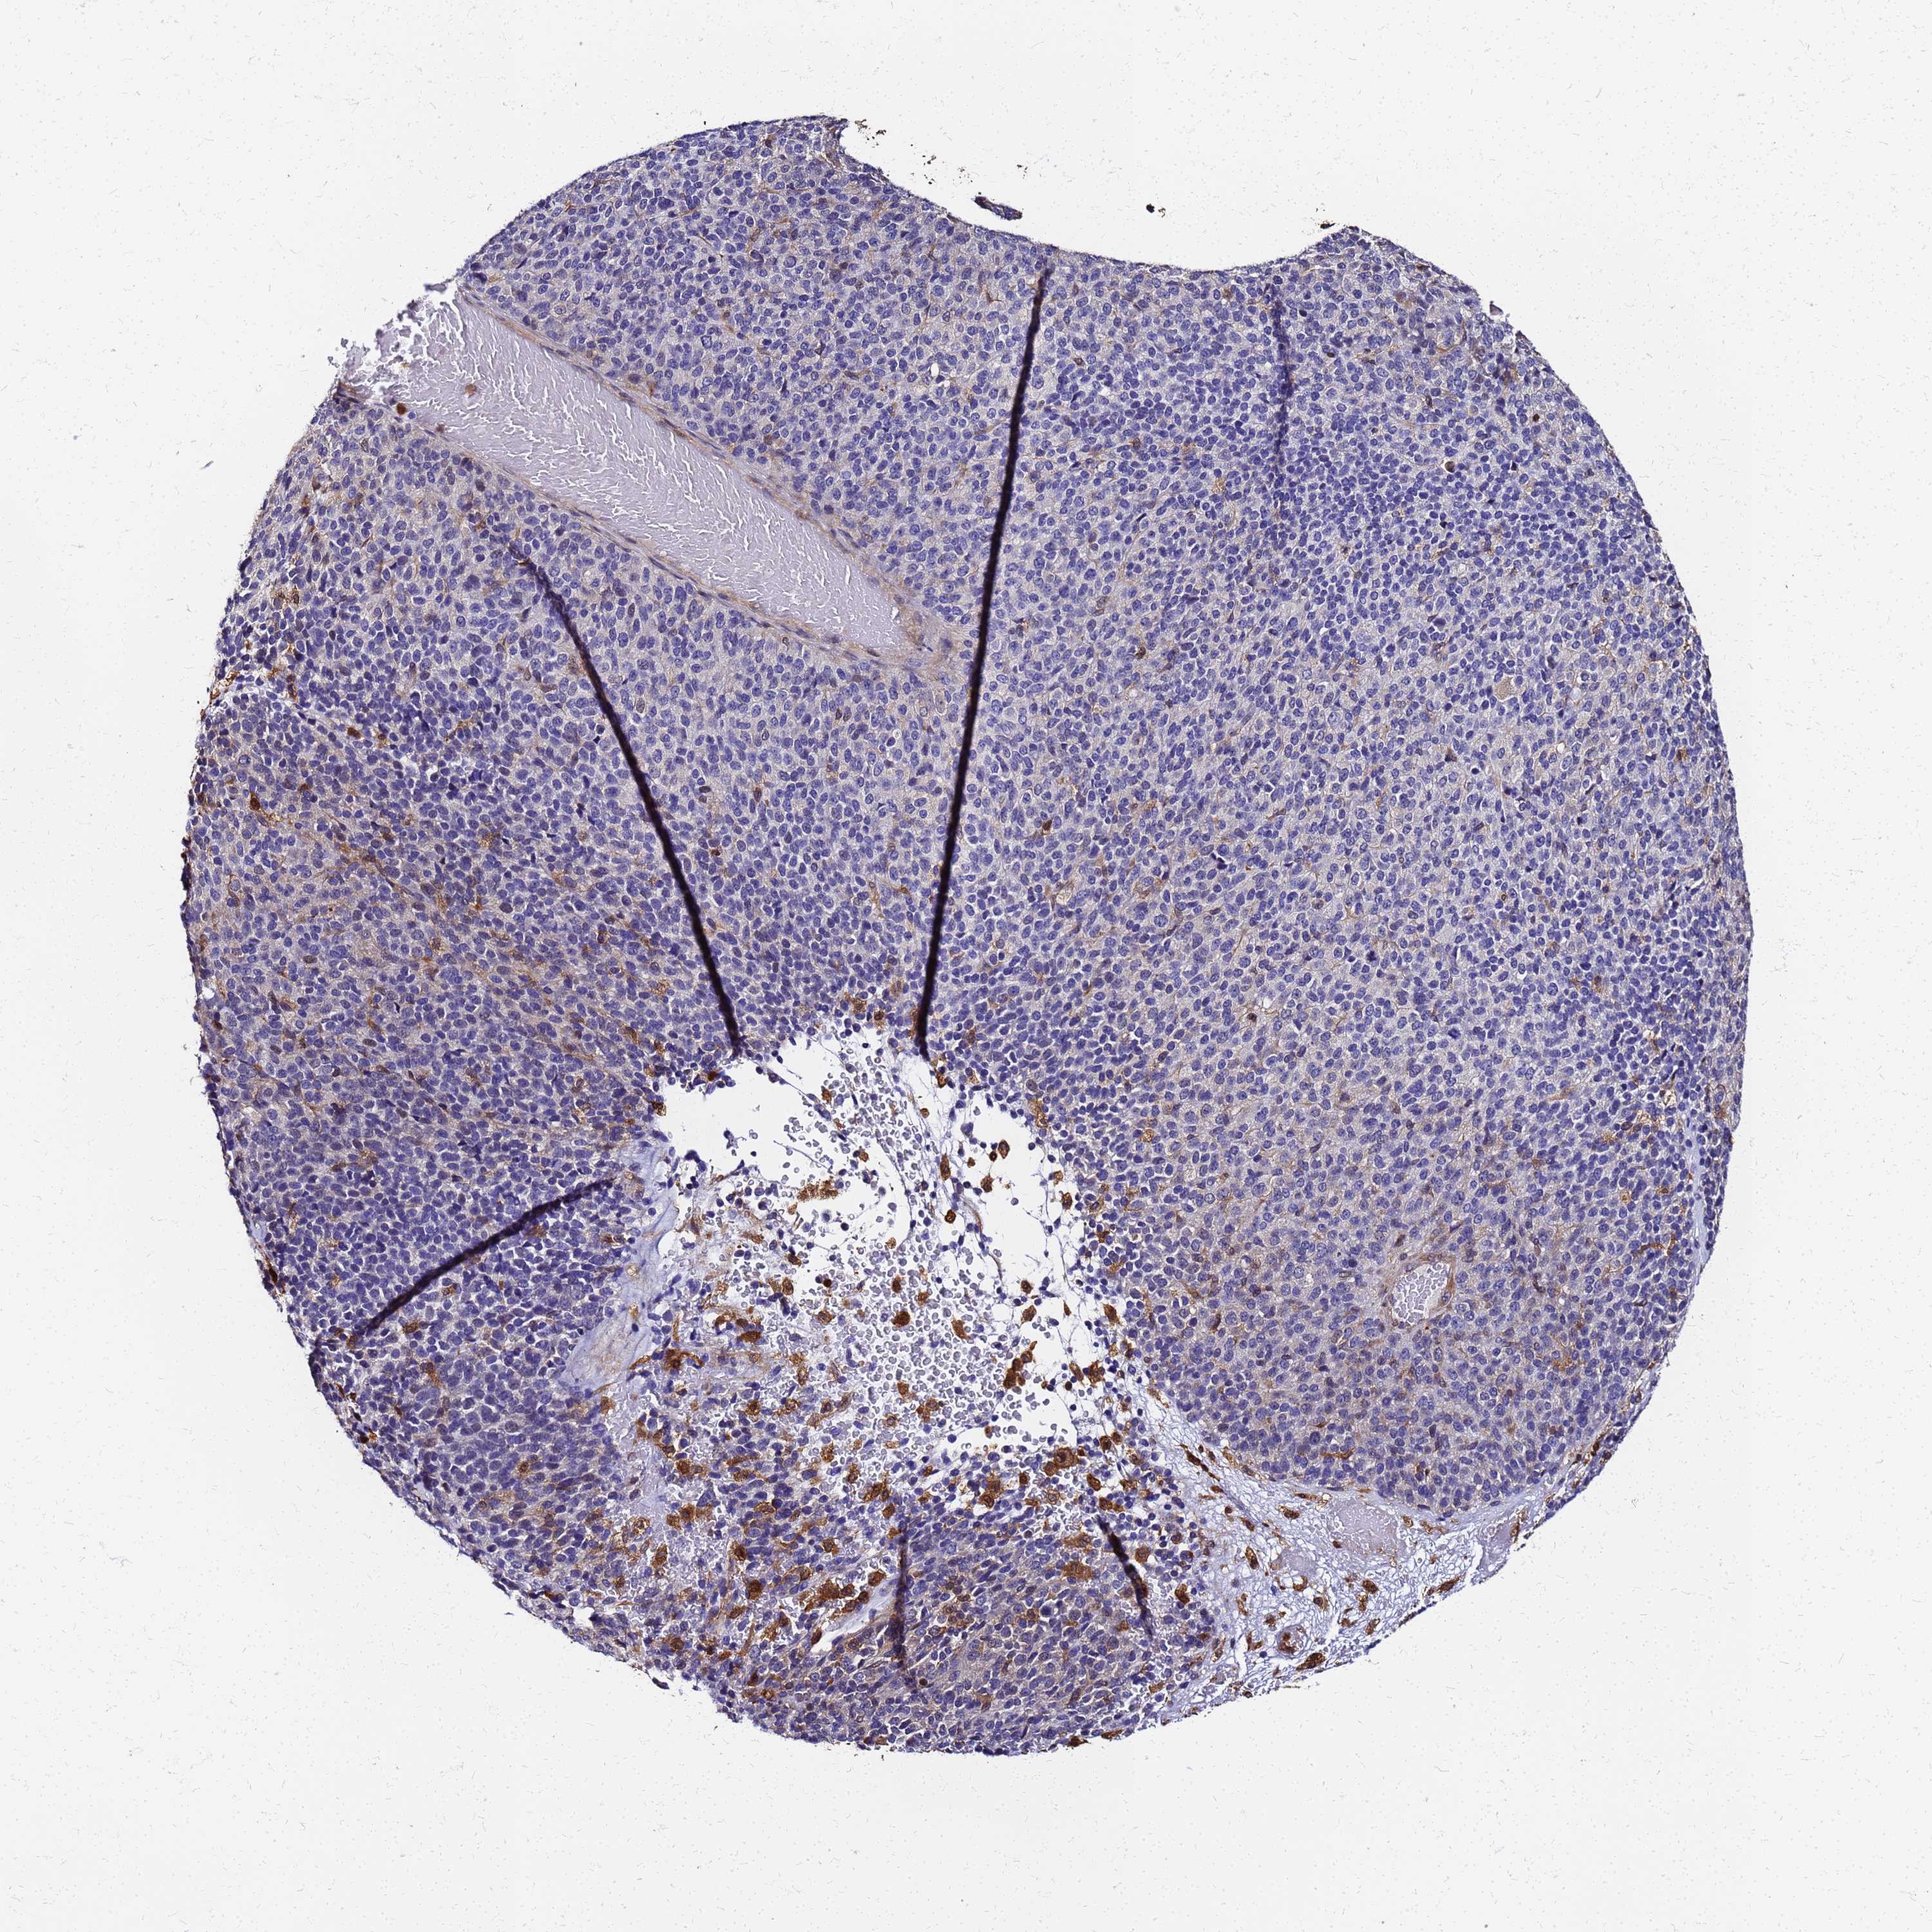

MELANOMA - Protein expressioni

A mouse-over function shows sample information and annotation data. Click on an image to view it in a full screen mode. Samples can be filtered based on level of antibody staining by selecting one or several of the following categories: high, medium, low and not detected. The assay and annotation is described here.

Note that samples used for immunohistochemistry by the Human Protein Atlas do not correspond to samples in the TCGA dataset.

Antibody stainingi

Antibody staining in the annotated cell types in the current human tissue is reported as not detected, low, medium, or high, based on conventional immunohistochemistry profiling in selected tissues. This score is based on the combination of the staining intensity and fraction of stained cells.

Each image is clickable and will lead to virtual microscopy that enables deeper exploration of all samples and also displays staining intensity scores, fraction scores and subcellular localization as well as patient and tissue information for each sample.

Antibody HPA042745

Antibody CAB034320

Staining

High

Medium

Low

Not detected

Intensity

Strong

Moderate

Weak

Negative

Quantity

>75%

75%-25%

<25%

None

Location

Nuclear

Cytoplasmic/membranous

Cytoplasmic/membranous,nuclear

Malignant melanoma, NOS

Malignant melanoma, Metastatic site